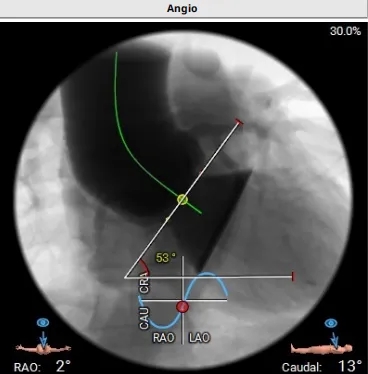

心脏角度:53°

初始造影确定无冠窦

瓣膜释放过程(可见窦部扭转带来的异常轴向)

完全释放瓣膜左右重叠下评估位置

左冠切线位下立体评估左冠深浅